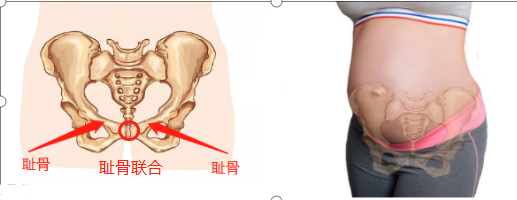

还有一个更扎心的事实是女性的膝关节天生不完美,一项对中国膝关节骨关节炎的患病率及危险因素进行的大样本调查发现,我国膝关节炎发病率女性为 10.3%,男性为 5.7%,女性明显高于男性。